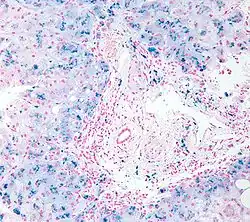

Micrograph of liver biopsy showing iron deposits due to haemosiderosis. Iron stain.

In general, the term hemosiderosis is used to indicate the pathological effect of iron accumulation in any given organ, which mainly occurs in the form of the iron-storage complex hemosiderin.[17][18] Sometimes, the simpler term siderosis is used instead.